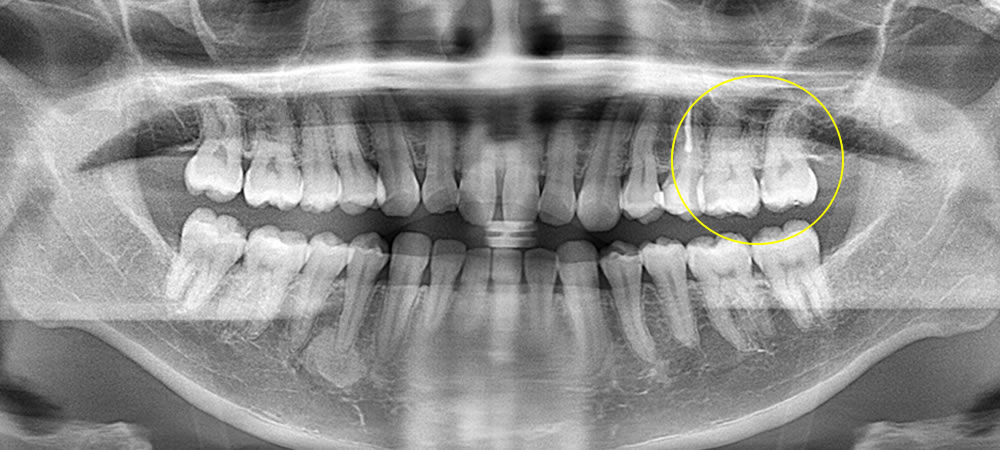

左上の奥歯2本に比較的大きな虫歯が確認されました。見た目では分かりにくい状態でしたが、レントゲン検査により虫歯が歯の内部まで進行していることが分かりました。

| 治療部位 | 左上6・7(左上の奥歯2本) |